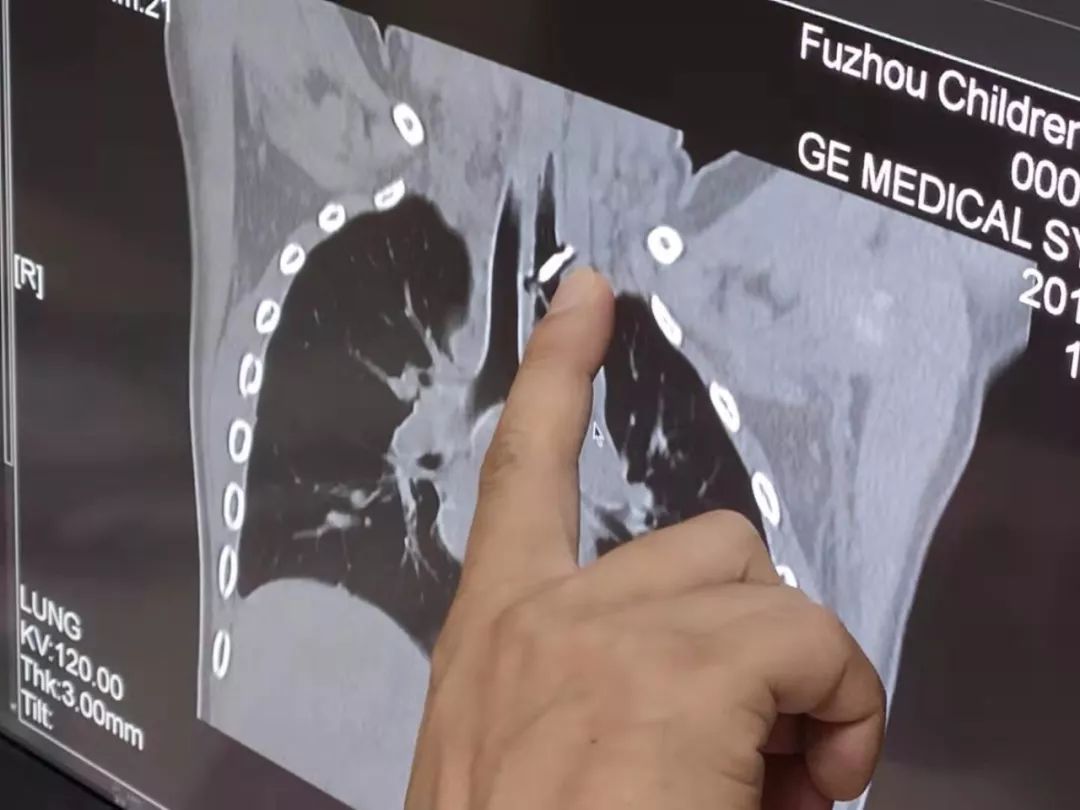

(网线钉嵌入食道)

接诊的福建省福州儿童医院消化内科副主任医师林卫东一看到CT片,也吓了一跳!当时只能看到小男孩位于食道部位的尖尖的钉子头正对着颈总动脉,手术风险较大。如果取出过程中,不慎刺穿食道,伤及颈总动脉,血液可能大量喷溅,患儿甚至有生命危险!当天晚上,立刻进行食道异物取出术,而且术前备足了足够的用血。虽然网线钉占据的位置奇特,而且有塑料有金属,还有凹槽,不过经过多科室通力合作,医生夹住“网线钉”,稍微用点巧力,终于顺利取出这枚“肇事”的网线钉!